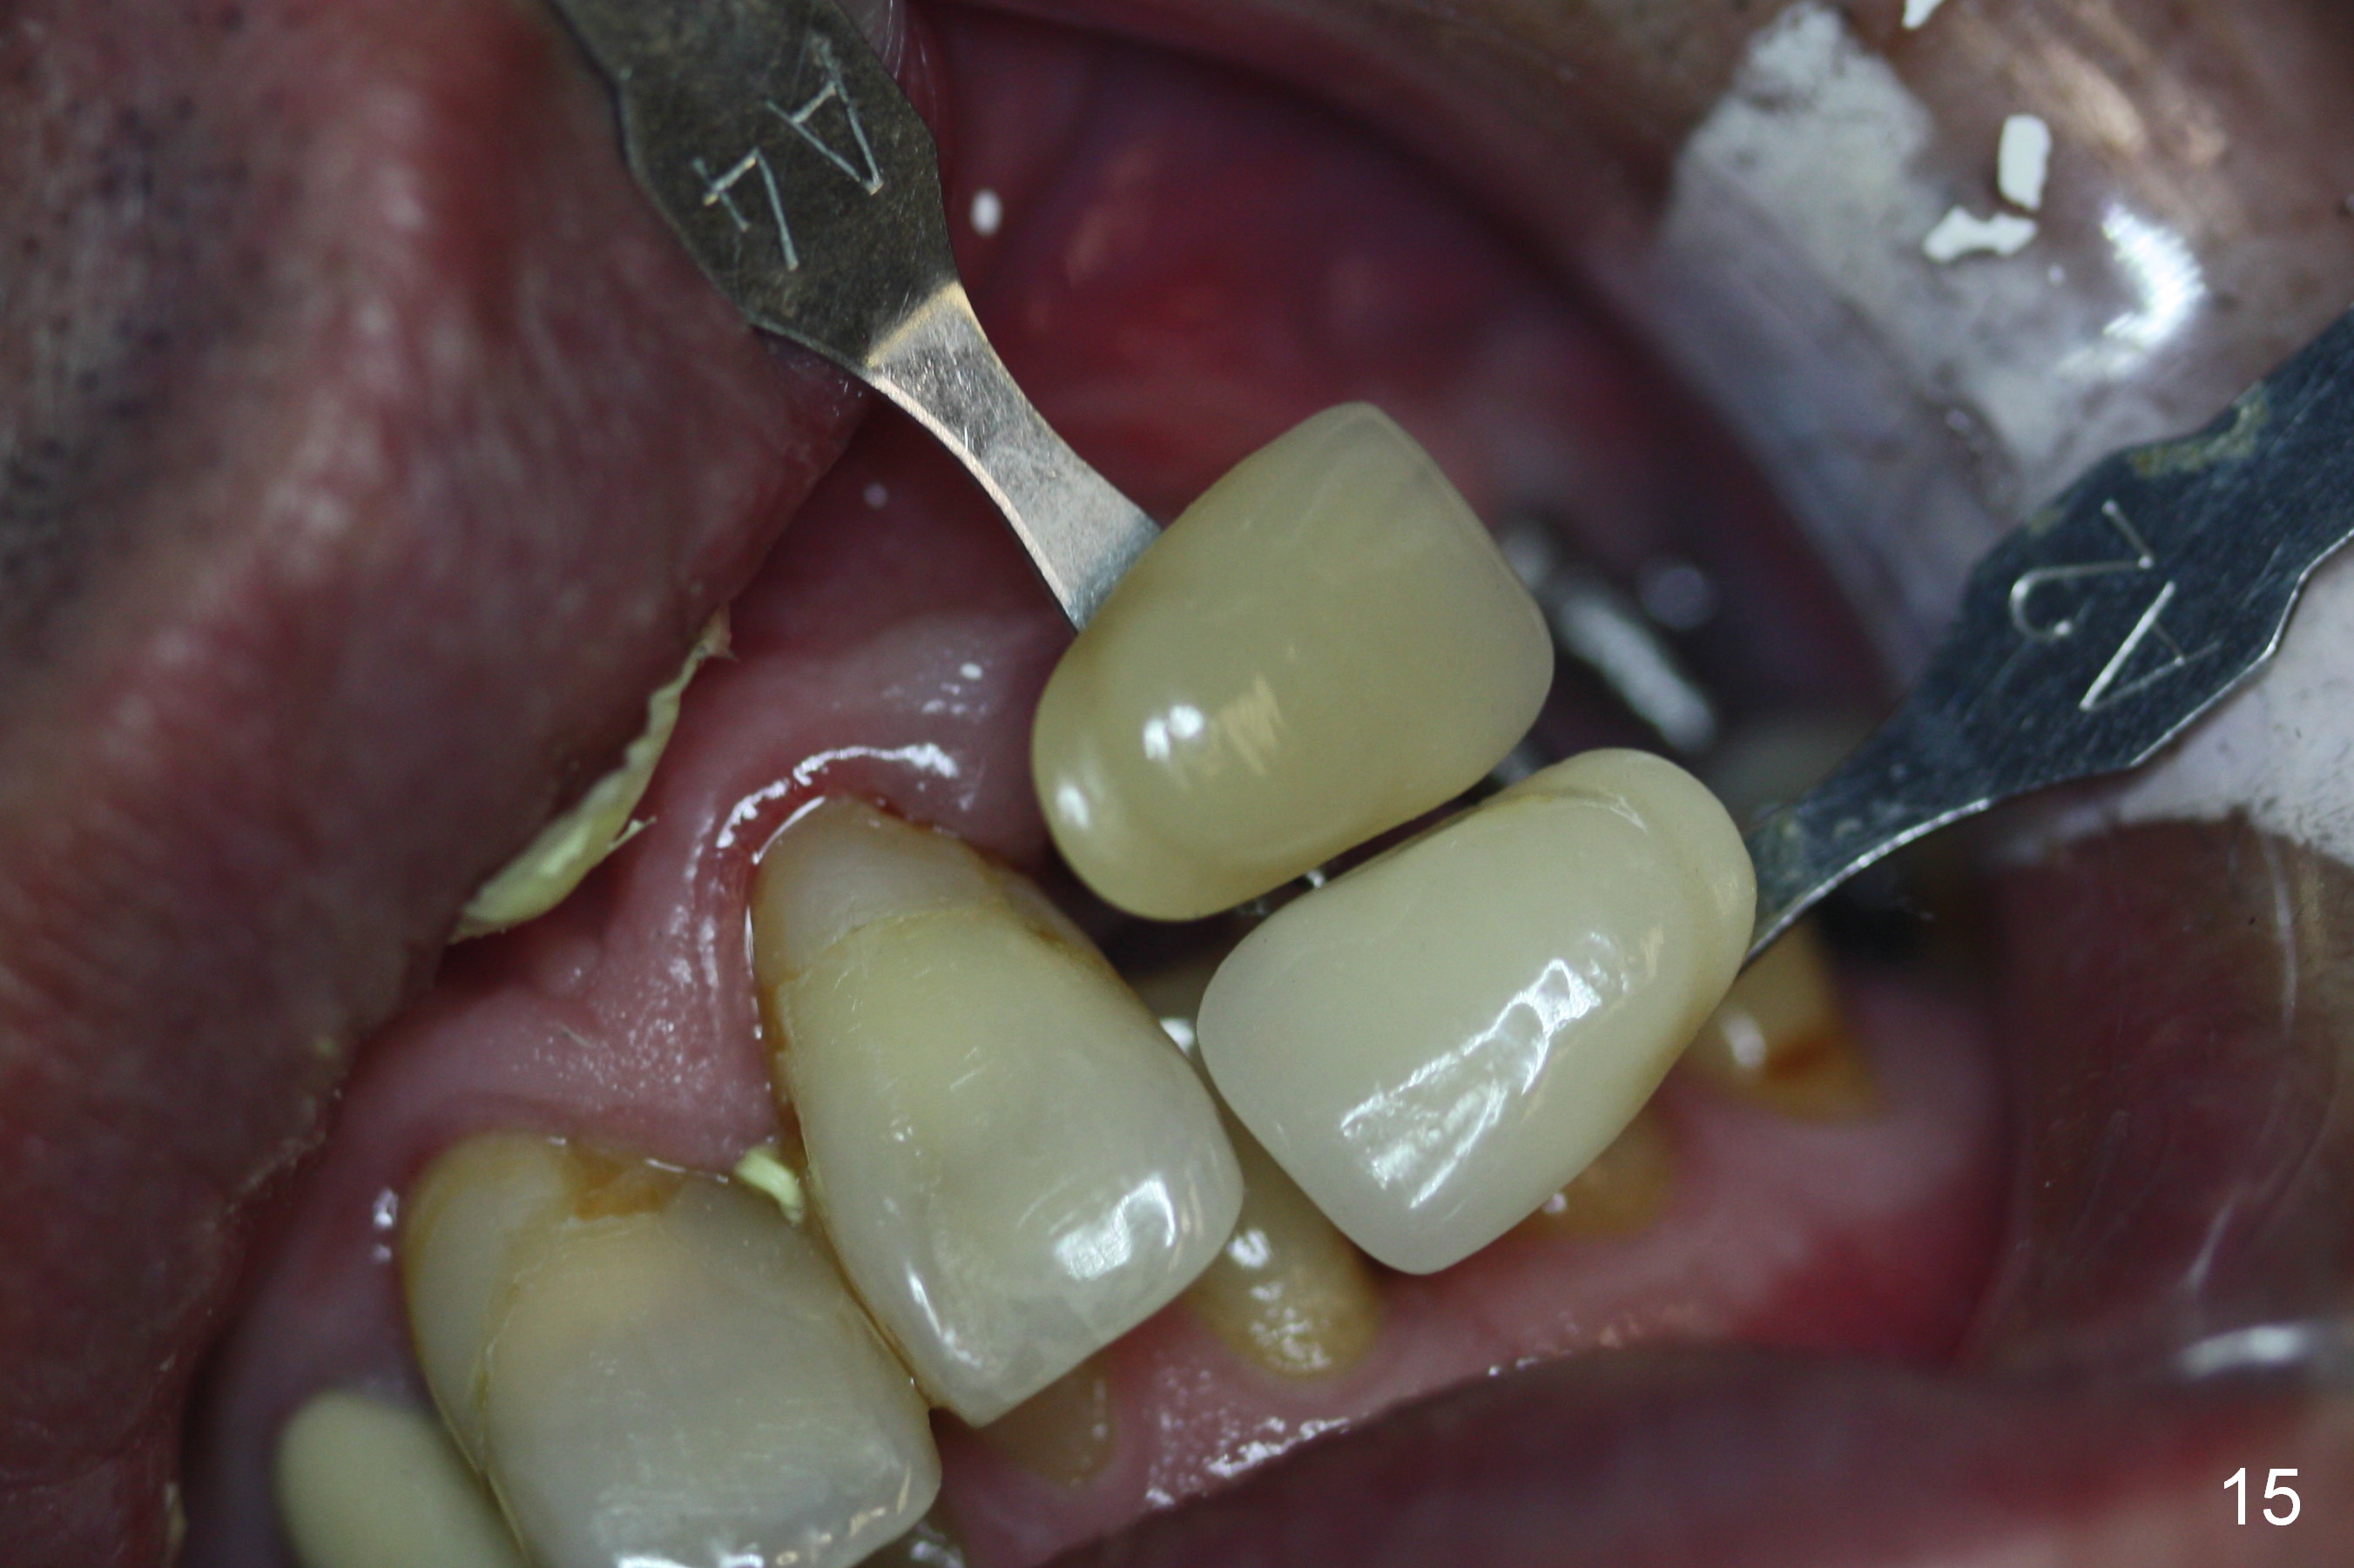

The patient returns for final restoration 3.5 months postop; it appears that the implants have osteointegrated (Fig.12,13).  After reprep, there is no gross buccal plate atrophy at #10 (Fig.14).